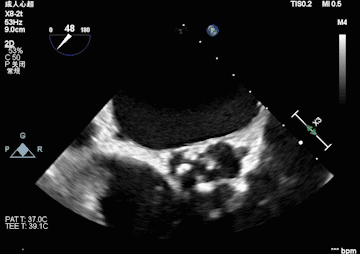

心脏超声

峰值流速:4.3M/s; 最高跨瓣压差:73mmHg; 平均跨瓣压差:43mmHg; 左室射血分数EF值:0.59; 左室舒张末期内径(LVD):5.3 cm。

主动脉瓣评估:三叶瓣,不均匀钙化,右无窦钙化交界处钙化严重,左冠瓣无明显钙化,瓣叶较厚,右无钙化明显。主动脉重度狭窄并中度关闭不全,二尖瓣轻中度狭窄,左房扩大,同时二尖瓣三尖瓣都伴有返流。

术前超声影像

术中球扩后超声影像

术后超声影像